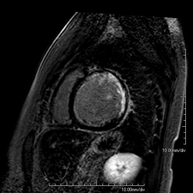

- Prostate MRI (endorectal prostate MRI + spectroscopy)

This non-invasive diagnostic procedure uses an electromagnetic field and radio waves (from a transmitter and receiver) to acquire high-definition anatomical images of the prostate gland. It is a radiation-free procedure. An endorectal coil is used to obtain images of the prostate with maximum anatomical definition, enabling a spectroscopic screening (molecular-level study to define malignant and tumour cells). A paramagnetic contrast study is also performed to provide better tissue definition. This screening takes about 40 minutes, during which time the patient should remain as still as possible. Prior preparation requires colon cleansing. This test is especially recommended for patients with suspected prostate cancer, known prostate cancer for tumour staging, prostate tumour localisation as a guide or map for biopsy, follow-up of patients with prostate cancer treated with surgery or radiotherapy, suspected recurrence of prostate cancer, etc.